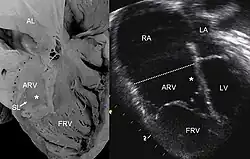

![]() Ecocardiografia de una anomalía de Ebstein: Abreviaturas: RA: aurícula derecha; LA: aurícula izquierda; ARV: ventrículo derecho atrializado; LV: ventrículo izquierdo. | ||